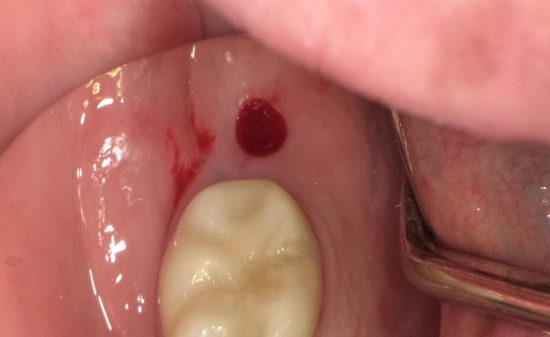

患者さんに教える口腔癌・前がん病変セルフチェック法

患者さんに教える口腔癌・前がん病変セルフチェック法口腔内は簡単に見ることができ、感覚は鋭敏ですから、早期に口腔内の疾患を発見することが可能です。しかしながら、実際に早期に発見される口腔癌を部位別で調べてみますと、歯肉は6%、頬粘膜は8%…